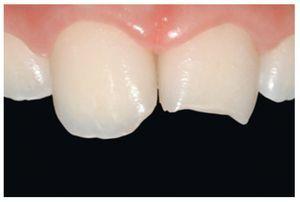

Figura 19 El caso, en una revisión después de un año.